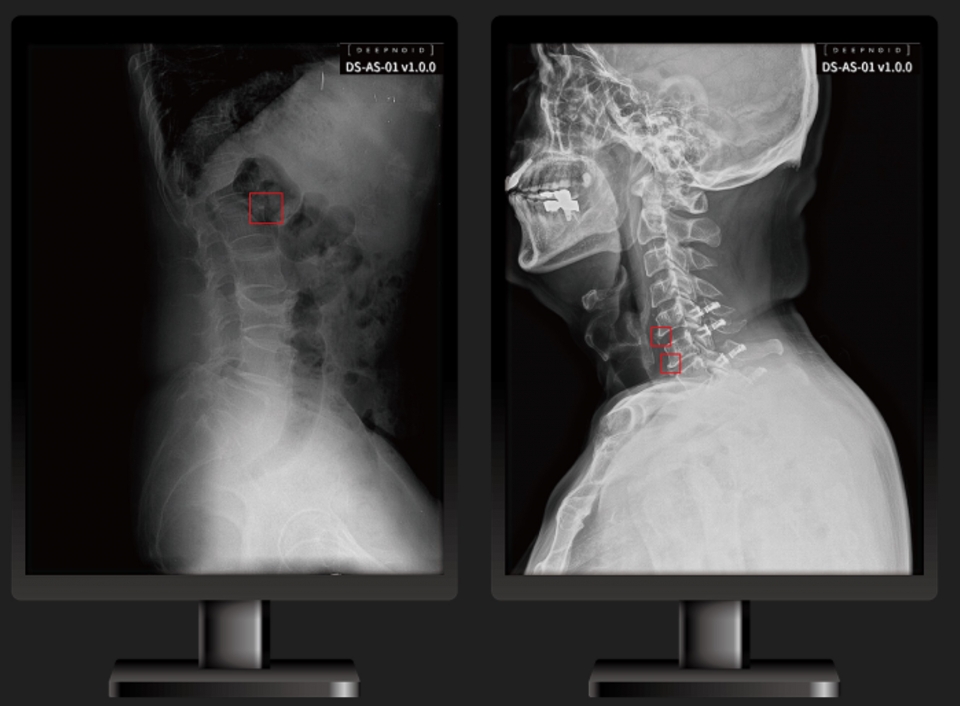

딥노이드가 척추부위 의료영상 AI 솔루션 '딥스파인(DEEP:SPINE, 모델명 DS-AS-01)'이 식품의약품안전처로부터 의료영상분석소프트웨어 인증을 획득했다고 3일 밝혔다.

‘딥스파인’은 척추부위를 측정하는 의료영상분석 소프트웨어로 척추 관절병등 진료를 보조한다. 특히 척추는 초기 X-Ray 상에서는 이상 소견을 발견하지 못하는 경우도 있어 병원을 찾아가도 대부분 허리 디스크부터 의심하게 되는데 MRI 같은 영상 검사로도 찾아내기가 쉽지 않아 이번 식약처 인증 받은‘딥스파인’이 척추 조기진단을 보조할 것으로 예상된다.

딥노이드가 식약처 인허가 받은 의료영상분석 소프트웨어는 흉부 X-ray영상에서 이상부위(폐경화, 기흉 등)를 검출해 의료인의 진단결정을 보조하는 딥체스트(DEEP:CHEST), 뇌신경두경부위를 촬영한 영상에서 이상부위(뇌동맥류등)룰 검출하는 딥뉴로(DEEP:NEURO), 척추 MRI 및 X-ray영상에서 이상부위(압박골절, 측만의 각도, 추간판 이상등)를 검출하는 딥스파인(DEEP:SPINE)등이 있다. 딥노이드는 자사의 의료영상 AI솔루션 ‘딥AI’와 자체 개발한 의료영상저장전송시스템(PACS) ' 딥팍스프로(DEEP:PACS PRO)를 상호연동을 통한 다질환검출 솔루션도 준비할 계획이다.